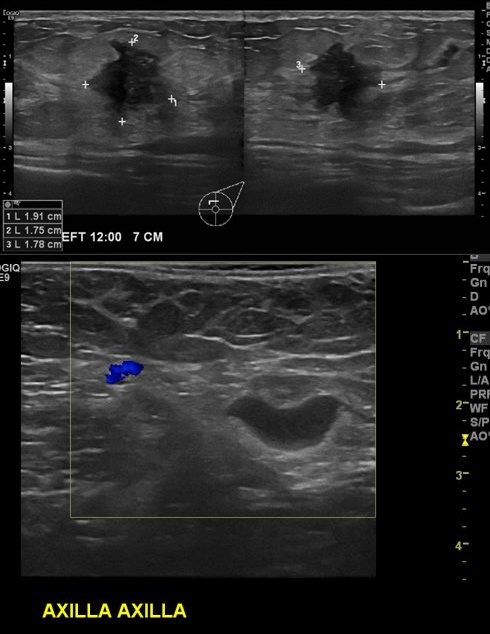

좌측 유방에 만져지는 멍울로 내원하신 40대 여성 분으로  좌측 유방 12시 방향에서

7cm 떨어진 거리의 만져지는 멍울 조직검사 시행 하여 좌측 침윤성 유관암 진단 되었

으며, 좌측 겨드랑이 림프절 비대 세침검사 시행하여 전이암으로 진단 되었습니다.